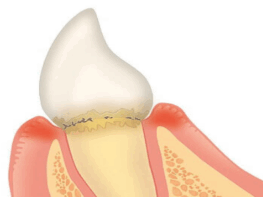

【歯肉炎】

歯垢(プラーク)がたまる

【軽度歯周炎】

歯茎が赤く腫れる

歯と歯肉の間に汚れが溜まって歯肉が炎症を起こして赤く腫れている状態。この段階ではほぼ痛みはありませんが、歯磨きの際に出血することがあります。

歯と歯肉の間に汚れが溜まって歯肉が炎症を起こして赤く腫れている状態。歯周ポケットがやや深くなっています。この段階ではほとんど痛みはありませんが、歯磨きの際に出血することがあります。歯を支える歯槽骨は少し溶かされ始めています。